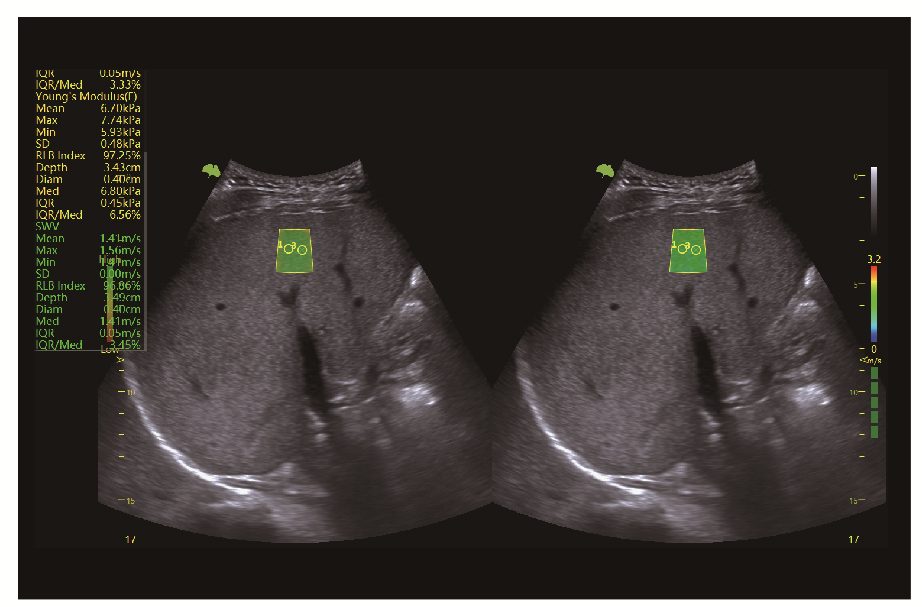

• VShear+ еластографія зсувної хвилі

Клінічні зображення, що демонструють якість діагностики та можливості обладнання

Клінічне зображення 4